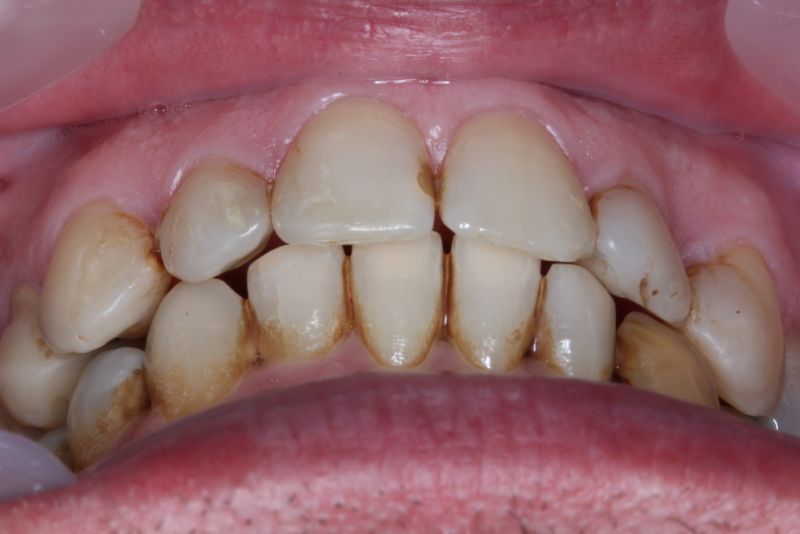

Der Patient hat von einem CMD Spezialisten in Bielefeld einen Aufbissbehelf erhalten. Den hat der Patient mit Zellstoff unterfüttert, weil der Aufbissbehelf so unterschiedlich hoch war, dass der Patient es vor Schmerzen mit dem Aufbissbehelf nicht ausgehalten hat.

Erkennbar ist die massive Abweichung der habituellen Bisslage von der neuromuskulär zentrierten Bisslage.